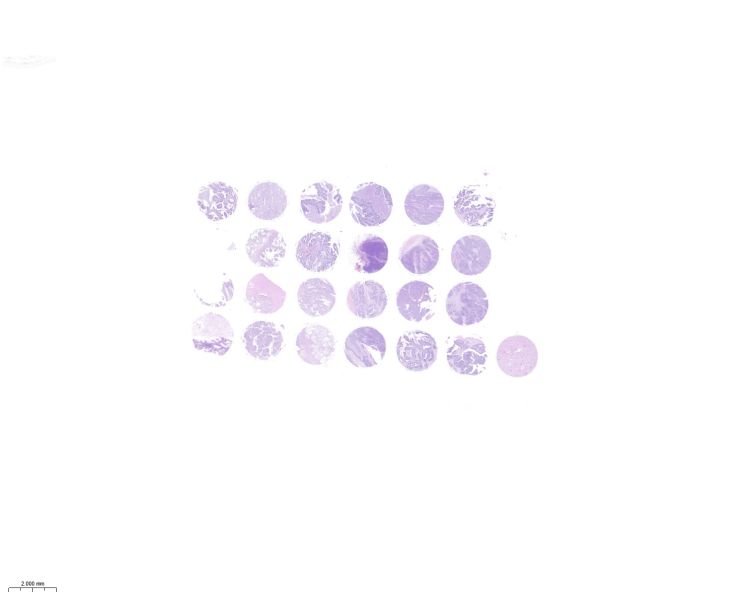

TMA Map